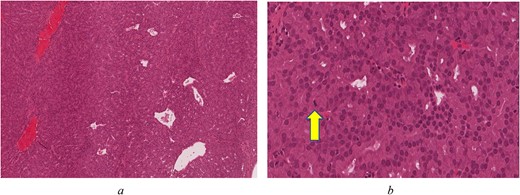

On immunohistochemistry the tumour was positive for CK7 (OV-TL 12/20), S100 (polyclonal), Ki-67 (MIB-1) ~10% with focal area reaching up to 20%. The tumour was negative for CK20 (KS20), CDX2 (ERP2764Y), P63 (DAK-p63), collagen IV (CIV22), P40 (ZR8), CK5/6 (D5/16B4), Calponin (CLAP), TFF-1 (SPT24), and Vimentin (V9). Histologic examination reveals an unencapsulated glandular growth, composed of numerous back-to-back small glands and few dilated cystic spaces with no intervening stroma. The glands are lined by a single layer of non-ciliated, cuboidal to columnar cells with uniform, round nuclei, abundant eosinophilic cytoplasm, and occasional prominent nucleoli. Mitotic figures are counted at 3 per 10 high power fields (Fig. 2a and b). No necrosis seen. Tumour cells were diffusely positive for CK7 and weakly positive for S100 (Fig. 3a and b). Other markers such as CK20, CDX-2 (Fig. 3c), p63, CK5/6, Calponin, TTF-1, and vimentin were negative. Ki-67 (MIB 1 clone) proliferation index was estimated at 10% with focal areas reaching up to 20% (Fig. 3d).

(a) Back-to-back glands with few dilated blood vessels and no intervening stroma (H&E*, original magnification ×80). (b) Compact glands with bland, monotonous, round nuclei. Arrow indicates a mitotic figure (H&E*, original magnification ×400) *Haematoxylin and Eosin.

The distinction between low-grade and high-grade and n-ITAC is crucial given the distinct clinical behaviour, prognosis, as well as management. Histological characteristics of high-grade n-ITAC include solid growth patterns with sheets of cells, poorly defined and irregular glandular patterns, hyperchromatism, mild to evident nuclear pleomorphism, and a high mitotic rate [3]. According to the histology report, the biopsied tissue was positive for mitotic figures (counted at 3 per 10 high power fields). This is especially noteworthy given that mitotic figures are believed to be extremely rare in low-grade n-ITAC and more prevalent in the more severe high-grade subtype [6].